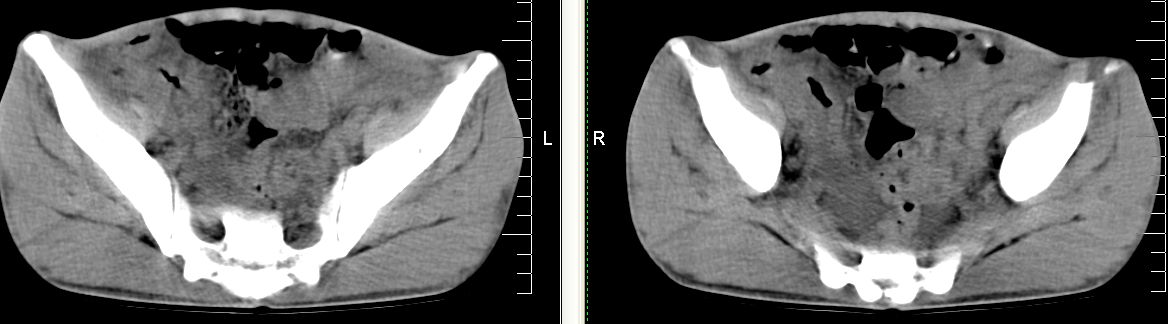

m 29 肺tb患者,目前诉下腹疼痛 t39度 腹韧,有压痛,可触及3x4cm包块

脾脏多发低密度灶,肠系膜及腹膜后见多发大小不等结节状影,右结肠旁沟见低密度影,结合病史考虑:脾结核,肠系膜及腹膜后淋巴结结核,少量腹水。

右侧结肠亦可见病变,腹膜后可见多发增大的淋巴结影,脾脏内示多个低密度结节灶,结合病史考虑结核性病变。

脾脏多发低密度灶,腹膜后及肠系膜根部多发淋巴结淋巴结肿大并部分相互融合,考虑tb.图象窗宽\\窗位没调整好,不清晰,另外,肠道准备亦不理想.

脾脏多发低密度灶,左侧肾上腺见块状病灶,密度不均,盲肠升结肠肠壁明显增厚,左下腹似可见肠壁增厚,肠系膜及腹膜后见多发大小不等结节状影,右结肠旁沟见低密度影,1淋巴瘤可能大,2结合病史考虑:脾结核,左侧肾上腺结核,肠系膜及腹膜后淋巴结结核,少量腹水待除外,